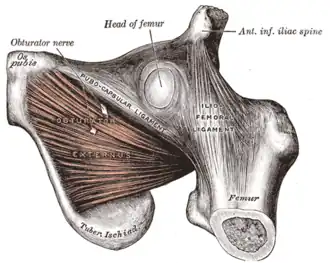

The obturator externus.

The obturator externus. -